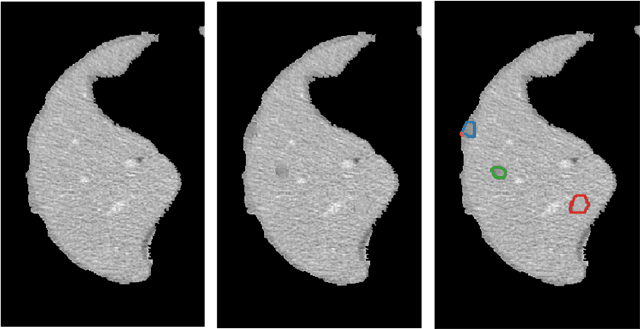

Abstract:Lesion synthesis received much attention with the rise of efficient generative models for augmenting training data, drawing lesion evolution scenarios, or aiding expert training. The quality and diversity of synthesized data are highly dependent on the annotated data used to train the models, which not rarely struggle to derive very different yet realistic samples from the training ones. That adds an inherent bias to lesion segmentation algorithms and limits synthesizing lesion evolution scenarios efficiently. This paper presents a method for decoupling shape and density for liver lesion synthesis, creating a framework that allows straight-forwardly driving the synthesis. We offer qualitative results that show the synthesis control by modifying shape and density individually, and quantitative results that demonstrate that embedding the density information in the generator model helps to increase lesion segmentation performance compared to using the shape solely.

Abstract:The success of supervised lesion segmentation algorithms using Computed Tomography (CT) exams depends significantly on the quantity and variability of samples available for training. While annotating such data constitutes a challenge itself, the variability of lesions in the dataset also depends on the prevalence of different types of lesions. This phenomenon adds an inherent bias to lesion segmentation algorithms that can be diminished, among different possibilities, using aggressive data augmentation methods. In this paper, we present a method for implanting realistic lesions in CT slices to provide a rich and controllable set of training samples and ultimately improving semantic segmentation network performances for delineating lesions in CT exams. Our results show that implanting synthetic lesions not only improves (up to around 12\%) the segmentation performance considering different architectures but also that this improvement is consistent among different image synthesis networks. We conclude that increasing the variability of lesions synthetically in terms of size, density, shape, and position seems to improve the performance of segmentation models for liver lesion segmentation in CT slices.